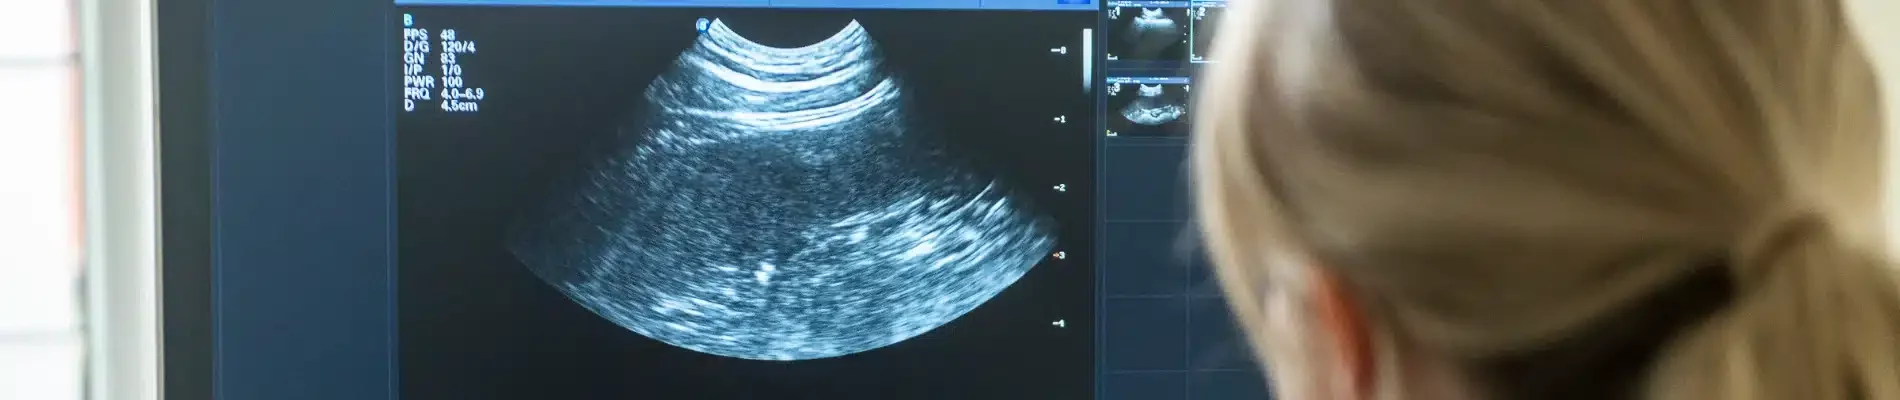

From routine blood tests and advanced imaging to specialist screenings, we offer a comprehensive range of diagnostic services designed to get a complete picture of your pet’s health. Every test is carefully analysed by our experienced team, and we take the time to explain the results in clear, straightforward terms. This approach ensures you fully understand your pet’s condition and the best steps to take, helping them stay happy, healthy, and comfortable.